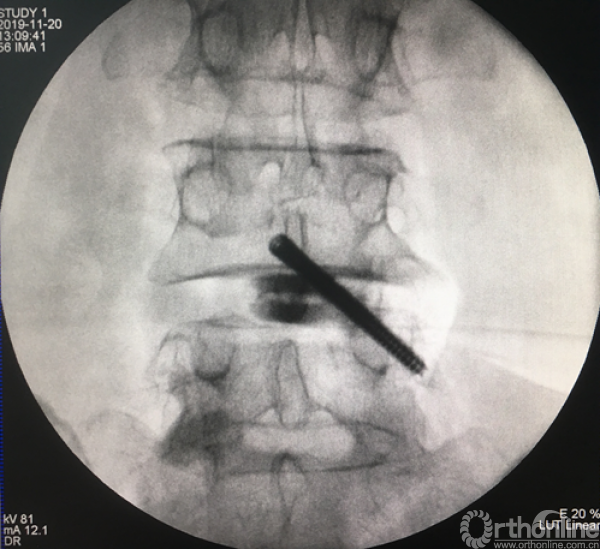

植入试模判断融合器大小

正侧位透视观察滑脱是否复位、融合器及植骨的位置